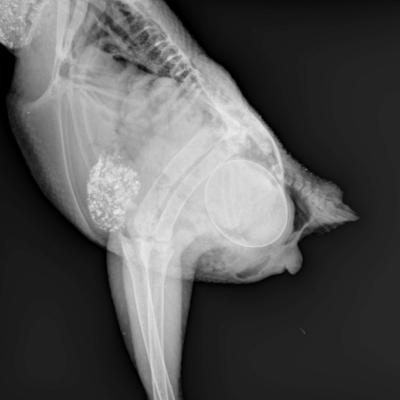

Corps entier d'Oiseau

Retention d'un oeuf sur un oiseau